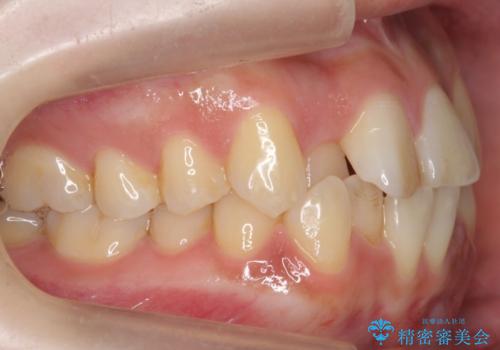

- 前歯のがたつき、受け口を主訴に来院。

上の前歯が二本裏側に入っていました。(反対咬合といいます)

上はワイヤー部分矯正、下はインビザライン(マウスピース)で部分矯正を行いました。

下の前歯を内側に入れる為、一本抜歯しています。

全体矯正で治そうとすると非抜歯ですとだいぶ口元が前に突出するのに加え、下の前歯が入りきらない可能性がありました。上下左右4本抜歯となるため、それを回避するのに下の前歯を1本抜歯して、下の前歯を確実に内側に入れています。